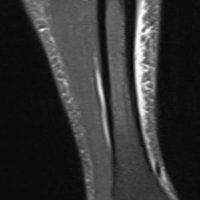

MRI is the most sensitive radiological examination (~88%). It may demonstrate a spectrum of findings ranging from normal to periosteal fluid to marrow edema to actual stress fracture. The medial cortex (+/- posterior cortex) is most commonly affected.